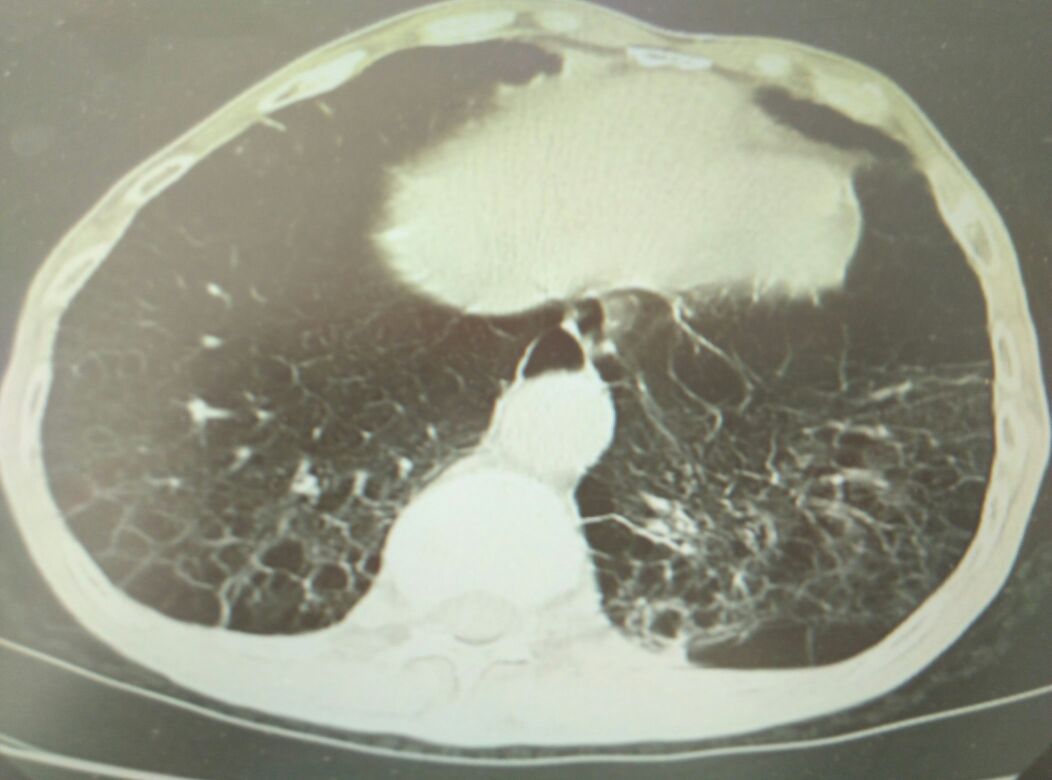

男,74岁,慢性咳嗽咳痰3年,加重3天,无浮肿

肺气肿

肺纤维化